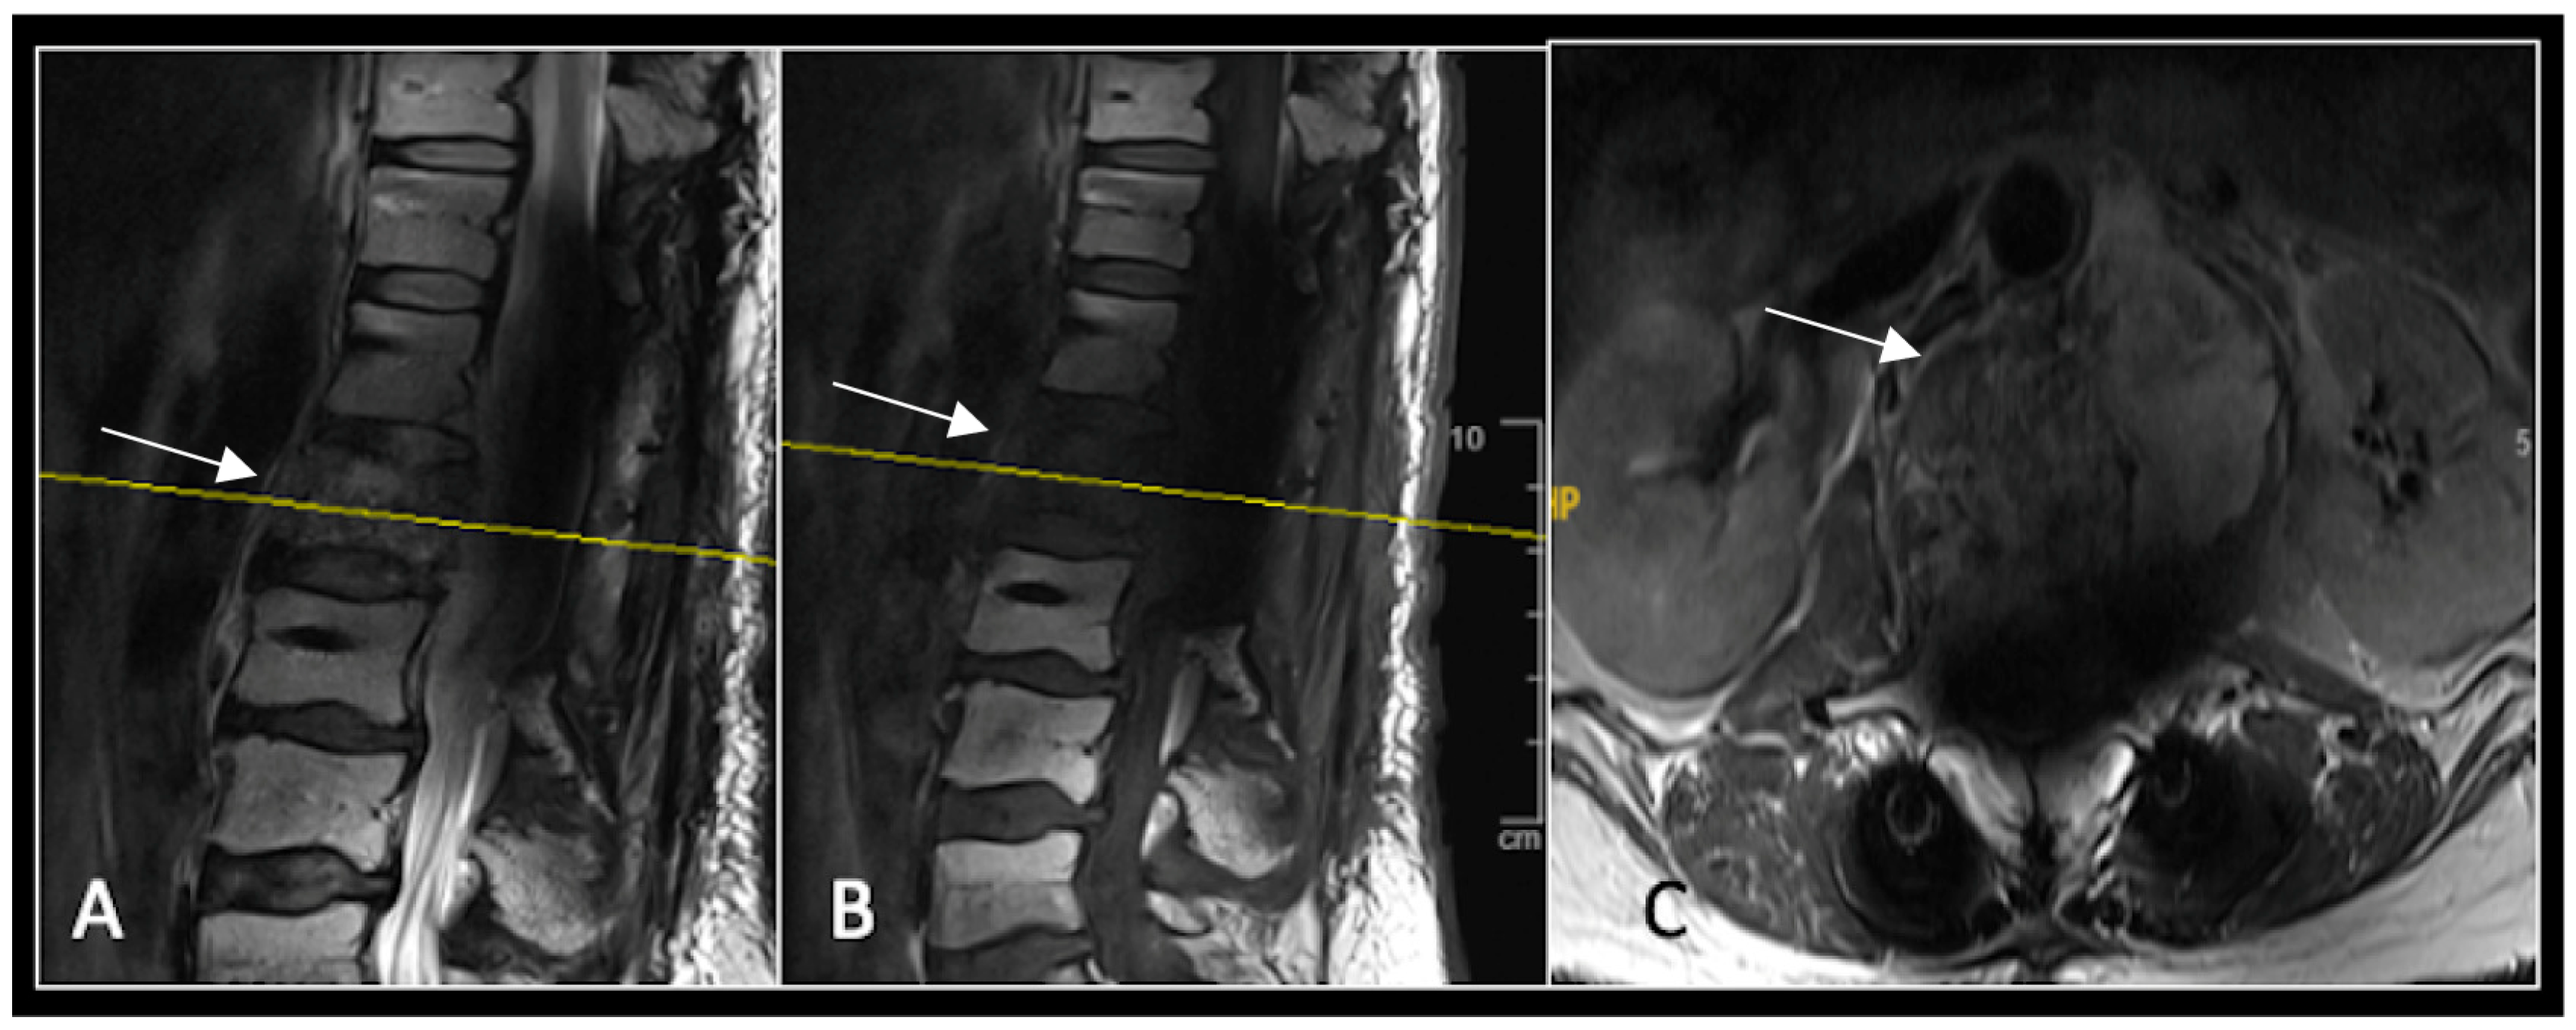

Figure 5.

MRI imaging following separation surgery. (A) T2W sagittal; (B) T1W sagittal; (C) T2W axial. Imaging shows removal of posterior lumbosacral elements with residual disease (arrow) within the S1 vertebral body but significant reduction in tumour dimensions. The yellow line on the sagittal images indicates the level at which the axial image was obtained.